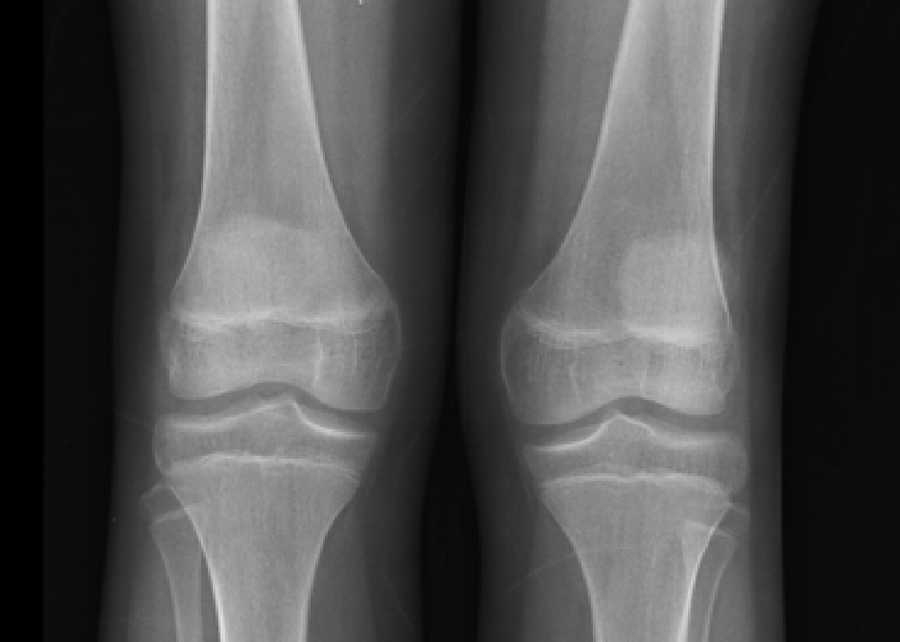

Las radiografías de cráneo se observaron normales, aunque los estudios de huesos largos con evidencia de descalcificación (Fig. 2).